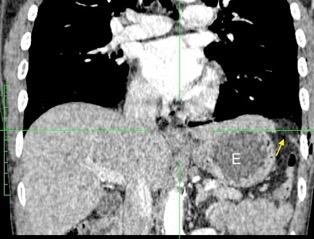

33. ENF. TORACOABDOMINAL. SEUDOQUISTE PANCREÁTICO

3 rasgos: Conexión entre mediastino y lesión pancreática. Derrame pleural Hallazgos de pancreatitis. Matsusue E et al.Three cases of mediastinal pancreatic pseudocysts. Acta Radiol Open. 2016 .